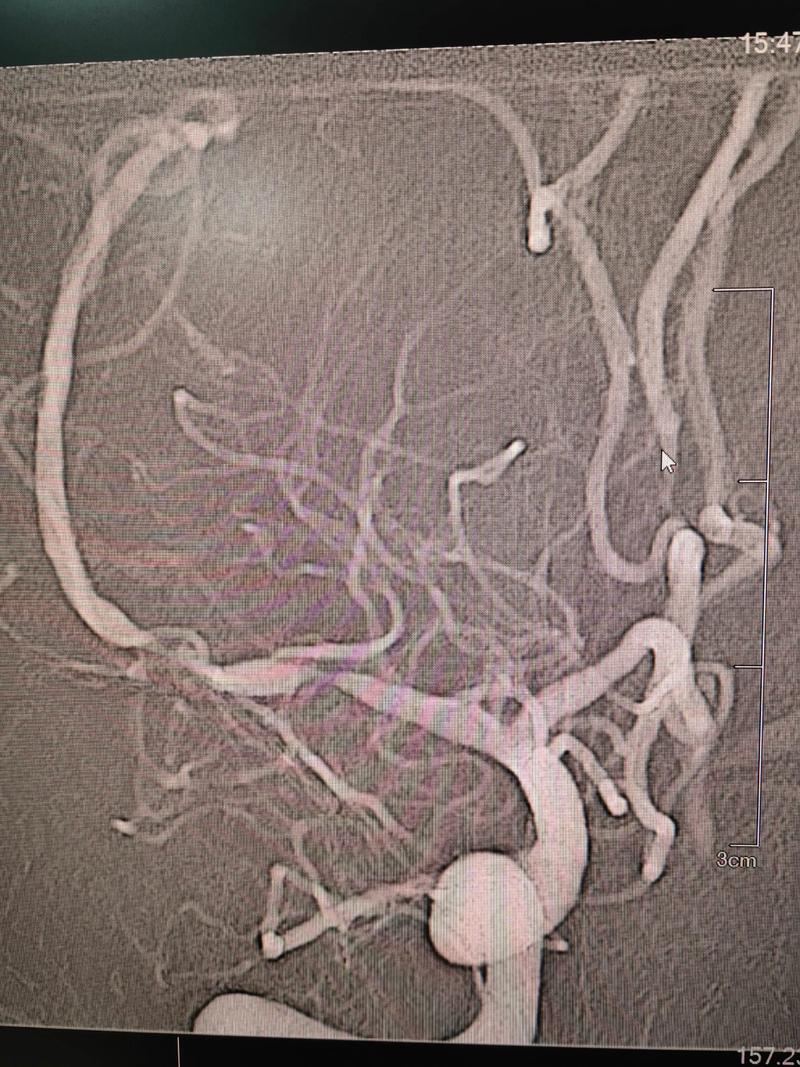

(图片来源网络,侵删)